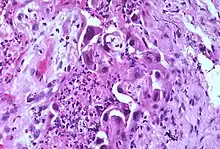

Atypia (from Greek, a + typos, without type; a condition of being irregular or nonstandard)[1] is a histopathologic term for a structural abnormality in a cell, i.e. it is used to describe atypical cells.

Features that constitute atypia have different definitions for different diseases, but often include the following nucleus abnormalities:[3]

- Enlargement

- Pleomorphism

- Nuclear polychromasia, which means variability in nuclear chromatin content.[4] (Polychromasia otherwise refers to a disease of immature red blood cells)

- Numerous mitotic figures